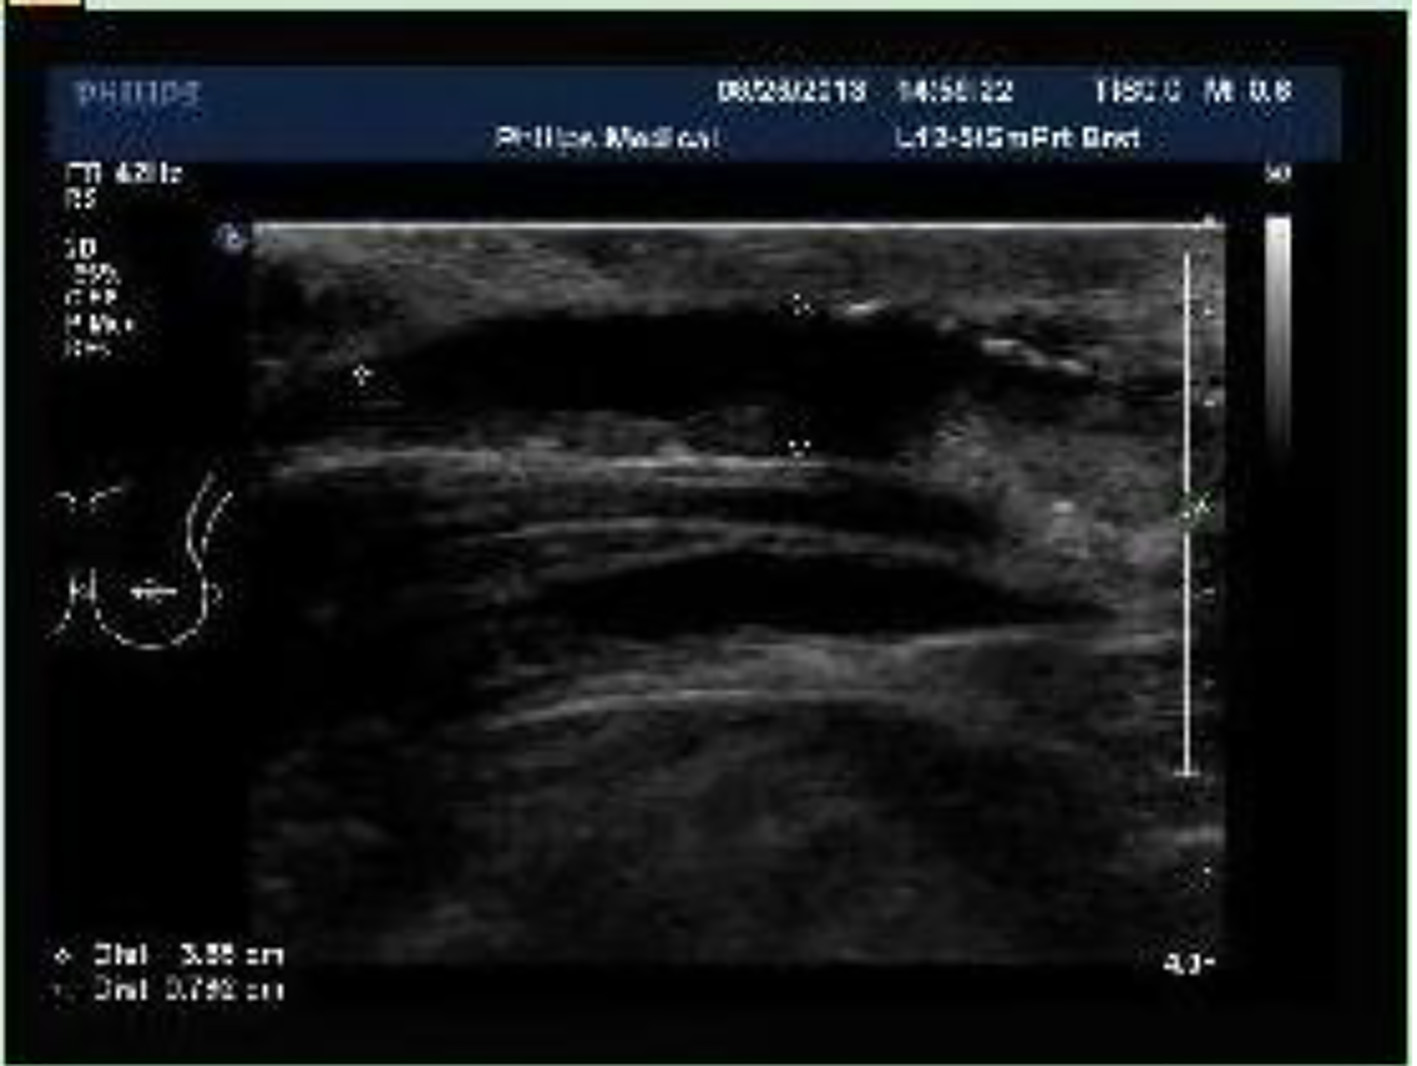

On September 17, 2014, the patient was hospitalized again 1 month after the right breast neoplasm was found. On physical examination, an approximately 3.0 × 2.0 cm neoplasm was palpable behind the areola in the 9 o’clock direction of the right breast with a pliable but strong texture, clear border, poor activity which seemed to be adherent to the skin. On color Doppler ultrasound, the cyst-solid space-occupying lesion was found in the 9 o’clock direction of the right breast with the BI-RADS of grade 4 (Fig. 4). On breast MRI, an abnormal signal was found in the right breast which may be the malignant tumor (Fig. 5).

Figure 4.

Click for large image

Figure 4. Breast color Doppler ultrasound (on September 17, 2014): a 2.1 × 2.0 cm cyst-solid space-occupying lesion was seen near to the nipple in the 9 o’clock direction of the right breast with the clear border and irregular form. Furthermore, the blood flow signal was found with the BI-RADS grading of 4a.